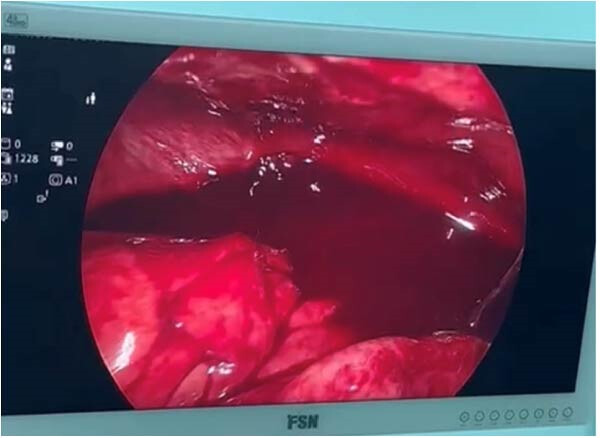

Во время диагностической лапаротомии были обнаружены околоободочно-кишечные борозды, заполненные гнойным экссудатом. Мобилизация слепой и восходящей ободочной кишки позволила выявить область, заполненную кровью, где впоследствии была найдена культя аппендикса (рис. 2А, В). Гнойный экссудат был удален, а оставшаяся ткань аппендикса резецирована.

Рисунок 2. (A, B) Интраоперационные снимки, на которых заметен гемоперитонеум и множественные спайки в правой подвздошной ямке.